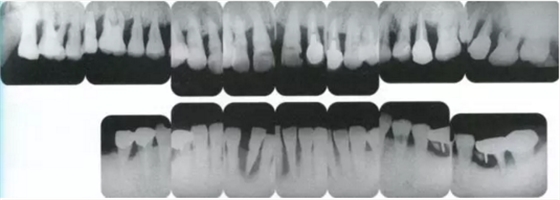

▲圖16-1~4 56歲,女性?;加腥谘乐苎浊蚁骂M磨牙區(qū)缺失,可以看到上頜前牙區(qū)有前突的現(xiàn)象。左上1和右上1無法保留。

▲圖16-5,6

▲圖16-7

▲圖16-5~7 將左上1和右上1拔除,下頜磨牙區(qū)植入種植體,全口進行牙周外科處理后,佩戴臨時修復體。圖16-7為佩戴臨時修復體后的狀態(tài)。由于左上2,3和右上2,3仍然前突,所以覆蓋較深。